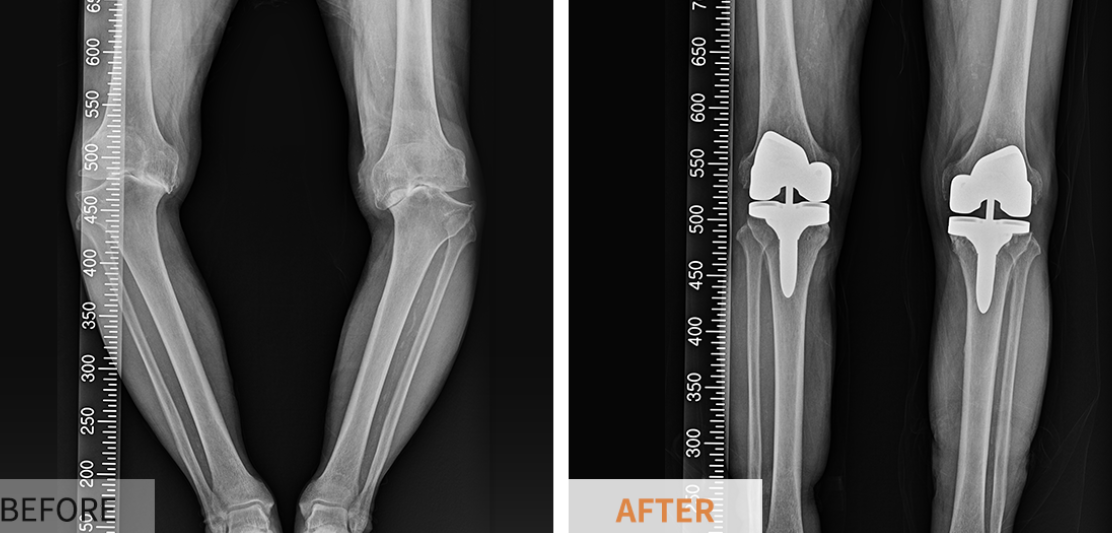

인공 슬관절 치환술이란?

인공 슬관절 치환술은 퇴행성 관절염이나 외상으로 인해 손상된 무릎 관절을 치료하기 위해 시행되는 수술로, 기능 회복과 통증 완화를 목표로 합니다. 손상된 관절을 제거한 후 특수 재질로 제작된 인공 관절을 삽입하며, 환자의 상태와 손상 범위에 따라 전체 치환술 또는 부분 치환술이 결정됩니다.

인공 관절은 무릎 관절의 복잡한 구조와 운동을 최대한 모방할 수 있도록 고안되었으며, 금속과 플라스틱으로 제작되어 있습니다. 가장 중요한 점은 인공 관절이 체내에서 거부 반응 없이 오랜 기간 안정적으로 유지될 수 있어야 한다는 점입니다. 따라서 개개인에게 가장 알맞은 보형물을 선택하는 것이 치료의 핵심입니다.